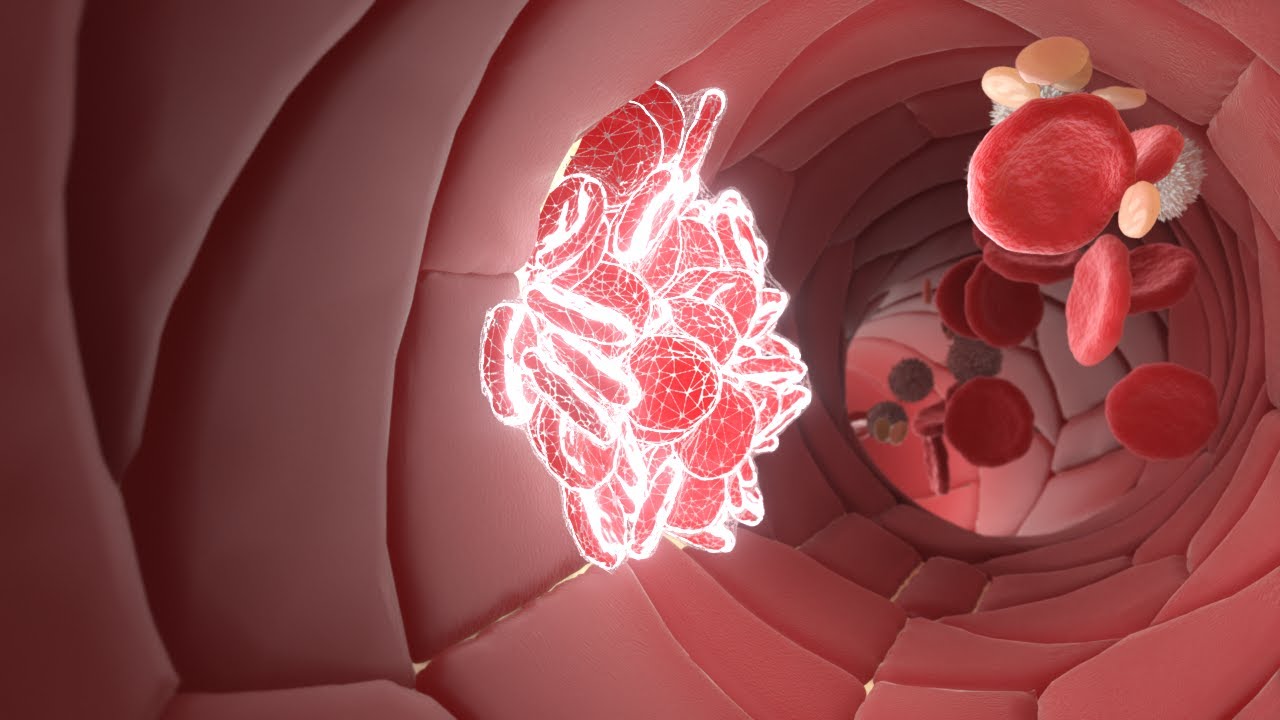

Hemostaz

4

0